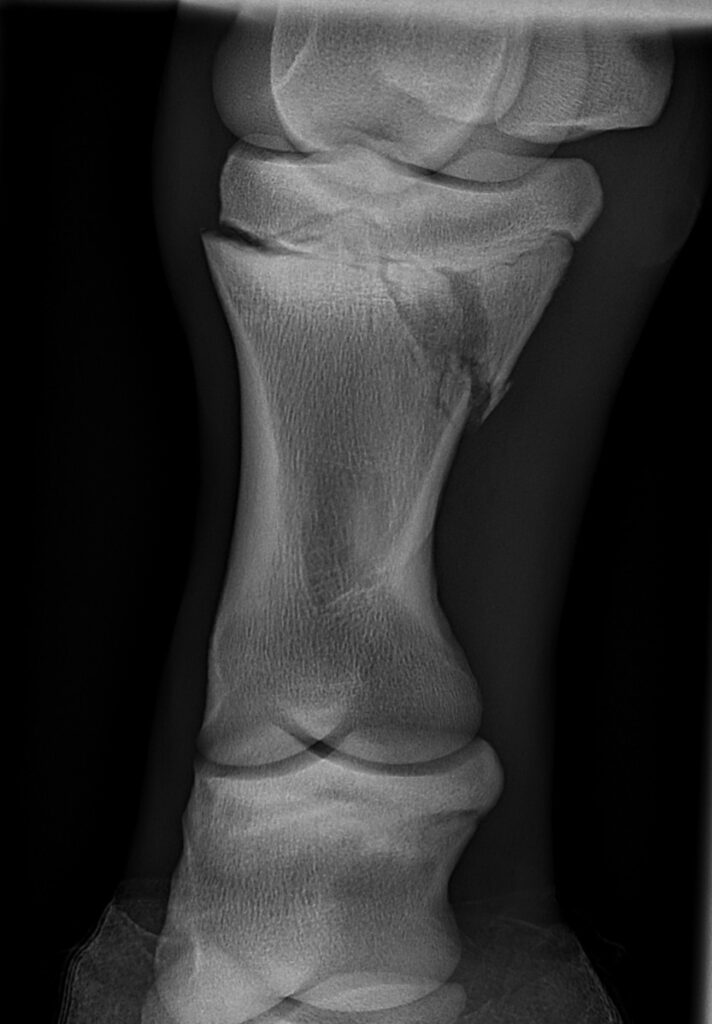

In this case study, a foal sustained a Salter-Harris type II fracture of the left hind proximal phalanx following a collision with a paddock mate, and subsequent fall. As a result, the foal was acutely lame on the affected limb. A radiographic examination confirmed the presence of the fracture, and the foal was referred to the hospital for further imaging and appropriate treatment.

Figure 1: DMPaL oblique radiograph of the left hind limb demonstrating a fracture involving the lateral aspect of the physis of the proximal phalanx.